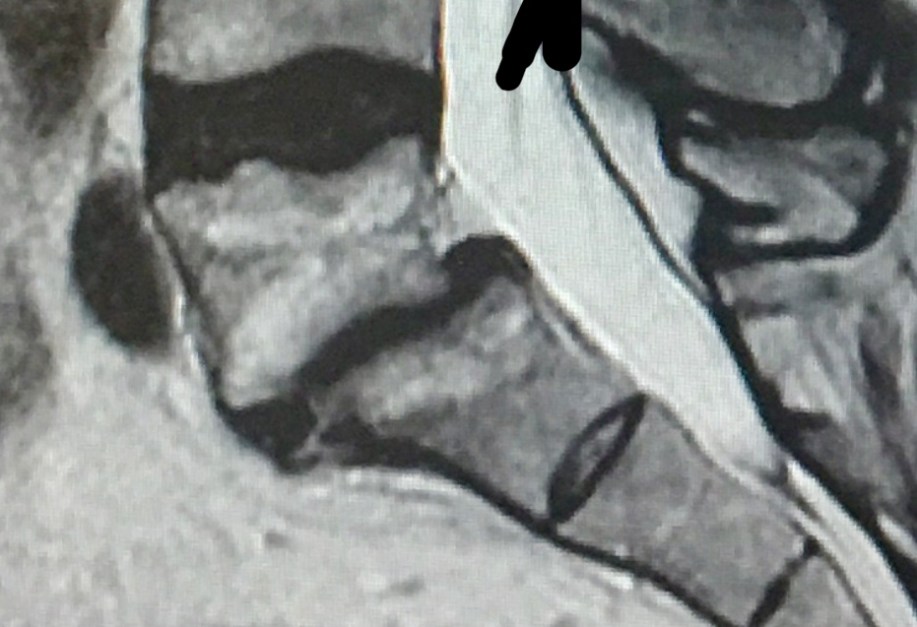

MR! 1 Posted by John Bartlett on April 26, 2019 Share this: Share on X (Opens in new window) X Share on Facebook (Opens in new window) Facebook Email a link to a friend (Opens in new window) Email Like Loading... This is an image for Operation Spider! (8th February 1993)…. Images navigation ← Previous Next →